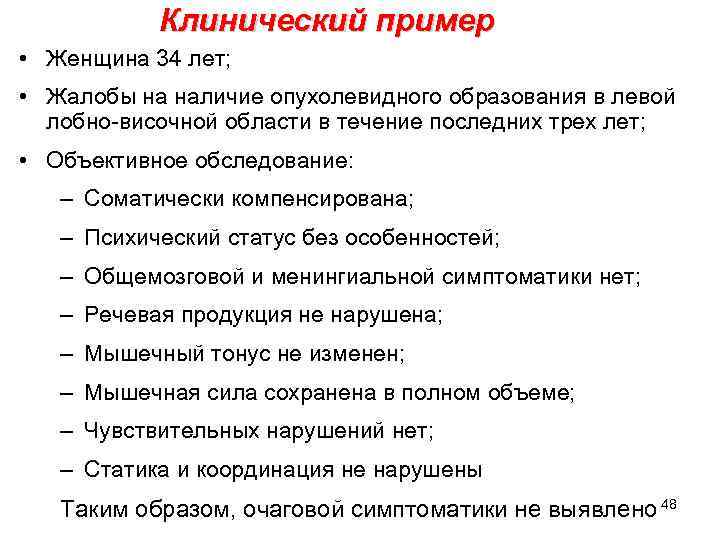

Клинический пример • Женщина 34 лет; • Жалобы на наличие опухолевидного образования в левой лобно-височной области в течение последних трех лет; • Объективное обследование: – Соматически компенсирована; – Психический статус без особенностей; – Общемозговой и менингиальной симптоматики нет; – Речевая продукция не нарушена; – Мышечный тонус не изменен; – Мышечная сила сохранена в полном объеме; – Чувствительных нарушений нет; – Статика и координация не нарушены Таким образом, очаговой симптоматики не выявлено 48